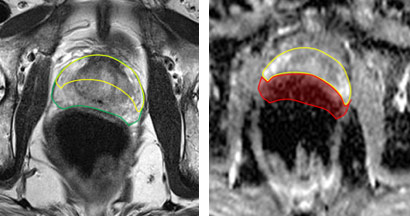

Erstes und zweites Bild: MRT-Bilder der Prostata aufgenommen mit einem 3 Tesla Scanner OHNE Endorektalspule. Die Bilder haben einen hohen Rauschanteil. Das Karzinom (Pfeil) ist weder auf den morphologischen T2-Bildern (links) noch auf den funktionellen ADC-Maps (rechts) gut dargestellt.Drittes und viertes Bild: 1.5 Tesla Bilder MIT Endorektalspule: Das Karzinom ist jetzt auf allen Bildern klar abgebildet.